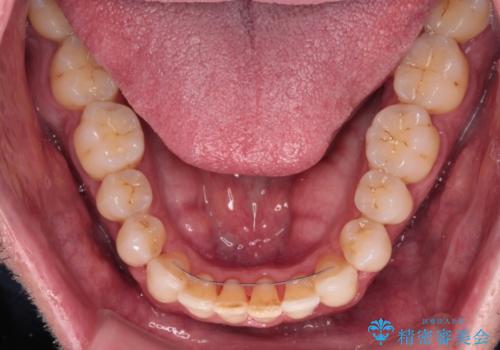

舌のトレーニング自体は簡単なものですが、無意識下でも舌が突出しないようにしなければならないため、毎日継続することが最大の難関です。

時間はかかりましたがトレーニングを頑張ってくださり、無事に前歯を接触させることができました。